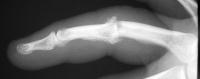

Clinical Example: Avanta proximal interphalangeal joint surface replacement arthroplasty

This young man had been treated for a rotating blade injury of the ring finger proximal interphalangeal joint. He had gross instability, pain and stiffness. These radiographs are before and after proximal interphalangeal joint reconstruction with the Avanta proximal interphalangeal joint surface replacement implant arthroplasty.

Lateral view:

Click for larger image